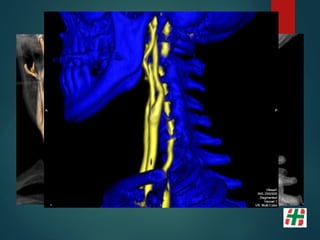

Disección Vascular

 Causa frecuente de Stroke isquémico en adultos jóvenes.

 Desgarro de la pared con formación de hematoma mural.

 Multifactorial, Trauma, infecciones, etc.

 Determinar extensión.

Mayor indicación de la secuencia TOF. Valor del crudo.